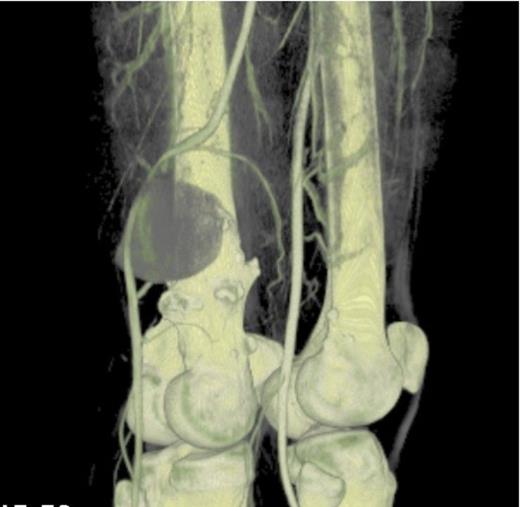

CT angiogram 3D reconstruction- Showing the bony exostoses and the popliteal aneurysm posterior to the right distal femur